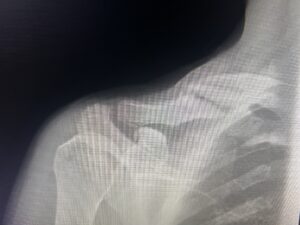

About 4 miles into the ride, I clipped my son’s rear tire and went down hard. I knew before I hit the ground that I was about to break my first bone. I landed forcefully on my shoulder and head. When I stood up, I could feel my collarbone moving in ways God never intended.

I try to make much more specific requests and prayers since that accident. I really messed up my shoulder! My clavicle was broken into 8 pieces, I tore my biceps tendon, had a concussion, and an enormous road rash that tore flesh off my leg.